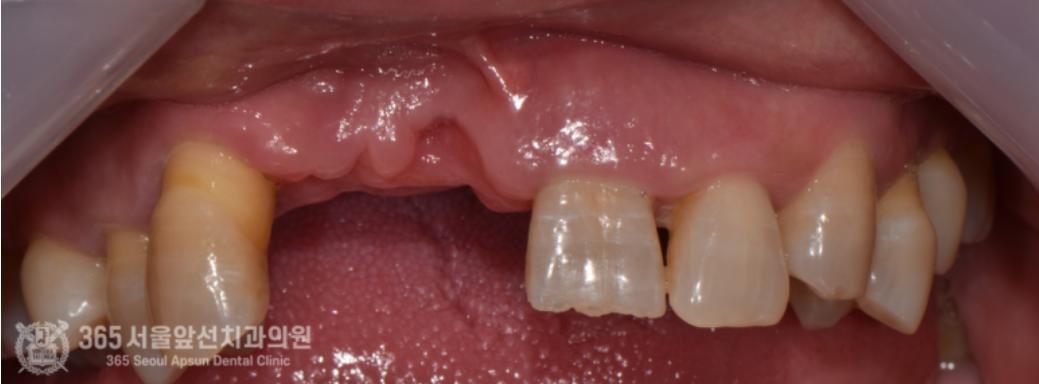

촬영일시 : 2024.08.06. 처음 내원 당시 촬영한 구강내 모습입니다. 치아가 많이 없고 남아있는 치아들 조차 상태가 좋지 않습니다. 이렇게 잇몸이 많이 부족한 경우에는, 잇몸이식을 통해 잇몸의 볼륨을 개선하고 보철물을 제작하는 것이 더 보기 좋은 보철물을 만들 수 있습니다. 촬영일시 : 2024.08.06. 오늘의 주제인 잇몸 이식을 시행했던 부위의 시행전 모습입니다. 치아가 발치되고 나면 서서히 잇몸이 줄어드는데요. 발치된지 얼마 지나지 않아서 아직은 치아가 있던 자리의 모양이 남아있는것을 보실 수 있습니다. 그러나 이 또한 시간이 흐르면 부피가 줄어들어 없어지게됩니다. 입천장에서 잇몸을 채취하여 앞니쪽에 이식을 진행했습니다.ㅎㅎ 잇몸을 입천장에서 채취해서 앞니쪽에 이식했구요~ 촬영일시 : 2024.12.01. 잇몸 이식 후 사진입니다.이식된 잇몸이 잘 생착되어가고 있습니다. 촬영일시 : 2024.12.01. 최종 보철물을 만들기 위해 임시보철물을 이용하여 잇몸 모양을 형성하고 있는 과정입니다. 잇몸이 어느 정도 안정화되면, 이후 임시보철물을 만들어서 잇몸모양을 형성해서 원하는 형태로 잡아주는 과정을 합니다. 촬영일시 : 2024.01.18. 잇몸 모양을 형성한 후, 최종적인 보철물을 제작하여 끼워드렸습니다. 촬영일시 : 2025.02.18. 아래쪽은 부분틀니를 원하셔서 부분틀니로 마무리해드렸습니다. 이번에 소개해드린 치료 증례는 잇몸 이식이라는 상당히 난이도 높은 술식을 통해 앞니의 미적 개선을 이뤄낸 증례입니다ㅎㅎ 환자분께서 매우 만족해하셔서 기쁜 마음입니다. 주안역치과 365서울앞선치과의원이었습니다. 감사합니다. [ 치료기간: 2024년 8월6일 ~ 2025년 2월 18일 ] ※ 365서울앞선치과의원의 모든 포스팅은 각 진료과 의료진이 직접 작성합니다. 365서울앞선치과의원 블로그의 임상 케이스 게시물은 환자분께 의학적으로 정확하고 상세한 정보를 드리기 위해 각 진료과 의료진이 직접 작성하며, 모든 증례 사진은 본원 의료진이 직접 시술한 증례를 촬영한 것으로, 의료법 제23조, 제56조에 의거하며 환자분의 동의를 얻어 포스팅에 사용하였습니다. 또한 해당 케이스는 본 환자분의 치료 결과이며, 환자 상태에 따라 치료의 결과는 달라질 수 있습니다. |